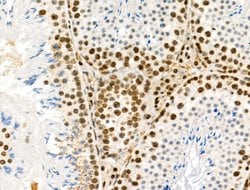

Invitrogen™ Phospho-PDX1 (Ser66) Polyclonal Antibody

Antibody detects endogenous levels of PDX1 only when phosphorylated at Ser66.

| Immunohistochemistry (Paraffin), Western Blot, Immunocytochemistry | |

| Human, Mouse, Rat | |